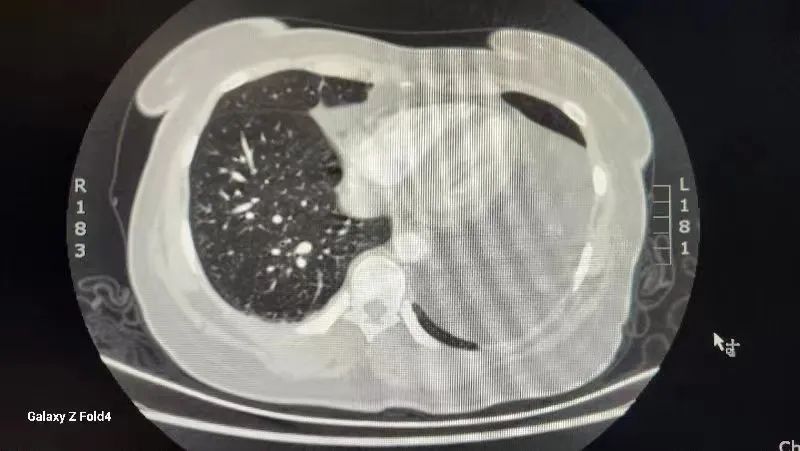

入住市中心医院胸外科后,胸CT检查示纵膈内心包左侧见团状脂肪密度影,较大层面大小约9.7*14.2厘米。完善纵隔磁共振等相关检查,根据检查结果高度怀疑纵膈内脂肪肉瘤。